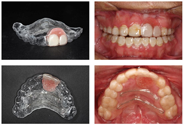

2017.04至2017.11:上下颌0.019*0.025NITI摇椅弓调整前牙转矩,调整个别托槽位置,垂直牵引加深前牙覆he,建立稳定咬合关系,0.019*0.025 SS结束主动矫治,制作带21,22牙义齿和横腭杆的透明压膜保持器,图6。